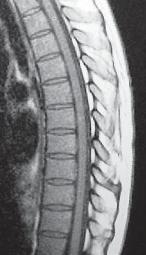

МРТ № 51

На МРТ № 51 наблюдается грудной отдел позвоночника с нормально выраженным физиологическим кифозом, межпозвонковыми дисками и спинным мозгом.